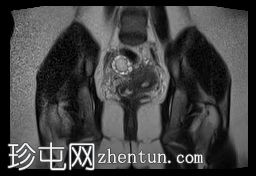

冠状位

T2加权像

双侧卵巢位置接近(卵巢相吻),左侧卵巢内可见一边界清晰的囊性病变,大小约3.1 × 2.7 × 2.9 cm,T1加权像呈高信号,T2加权像可见暗点征及内部暗点征。以上MRI特征符合卵巢子宫内膜异位囊肿的诊断。

右侧卵巢可见一囊肿,大小约为 2.8 × 2.0 × 2.2 cm,T1 加权像呈高信号,囊内可见液-液平面,提示囊内含有不同时期的出血性物质。由于对侧卵巢存在典型的子宫内膜异位囊肿,且该囊肿无强化,影像学表现强烈提示为另一子宫内膜异位囊肿。

双侧卵巢均可见多个小卵泡。